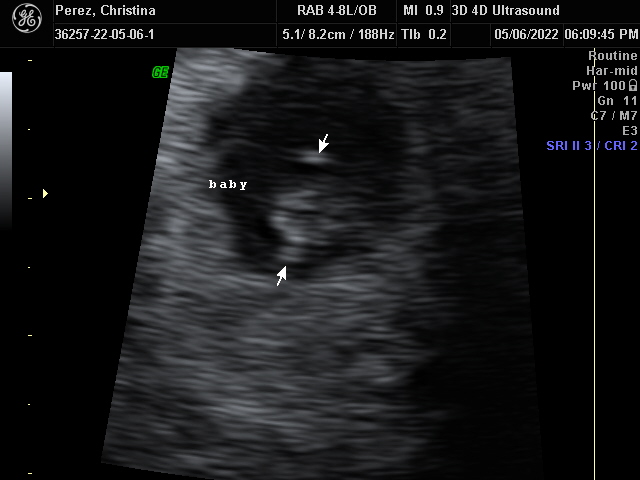

Our Gallery

Explore beautiful moments captured during our 3D and 4D sessions.